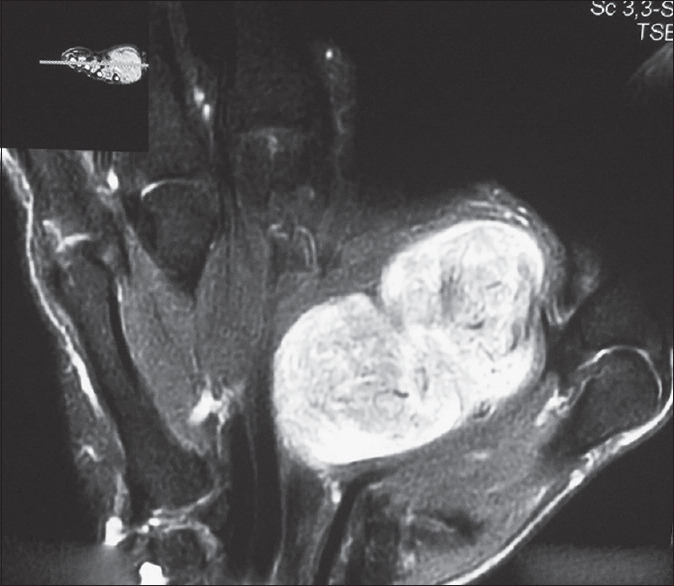

神经鞘瘤是最常见的周围神经良性肿瘤,但在成人中很少见。在出现疼痛、感觉异常和刺痛等症状之前,它们的生长速度极其缓慢。四肢巨大的神经鞘瘤会严重影响生活质量。通过正确的诊断,可以切除肿瘤,保留神经功能,复发的风险很低。本文报告一例成年男性右手鱼际隆起的症状性巨大神经鞘瘤。

Schwannomas are the most common benign tumors of peripheral nerves but are rare in adults. They have an extremely slow rate of growth before the onset of symptoms such as pain, paresthesia, and tingling. Giant schwannomas of the extremities can significantly affect the quality of life. With a correct diagnosis, the tumor can be extirpated with preservation of nerve function and a very low risk of recurrence. A case of a symptomatic giant schwannoma on thenar eminence of the right hand in an adult male is discussed in this report.